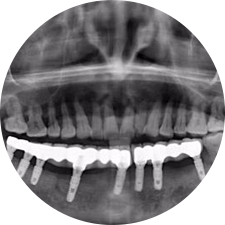

口腔種植是將人工牙根通過(guò)手術(shù)植入牙骨內(nèi),獲得牙槽骨牢固的支持,通過(guò)特殊的裝置和方式連接牙修復(fù)體,獲得與天然牙功能、結(jié)構(gòu)以及美觀相似的效果。

河北惟德口腔醫(yī)院擁有國(guó)內(nèi)豐富的半口/全口、即刻負(fù)重種植案例,十八年案例跟蹤分析,總結(jié)梳理出的各種不同類型的種植案例,Nobel種植體系針對(duì)半口/全口缺牙患者,通過(guò)4-8顆種植體可快速達(dá)到牙齒重建,不僅植入種植體較少,節(jié)省費(fèi)用,手術(shù)時(shí)間更短。

術(shù)前患者CBCT口掃1:1三維重建,模擬手術(shù)過(guò)程及預(yù)測(cè)術(shù)后治療效果,確定每顆植體植入的適合的種植位點(diǎn)、深度及角度,有效避免損傷頜骨重要解剖結(jié)構(gòu),提高手術(shù)準(zhǔn)確度與安全性。

Noble口腔種植體系基本不受年齡限制,適用于缺牙修復(fù),也適用于牙槽骨萎縮、骨質(zhì)疏松、高血壓、糖尿病、超高齡的患者,即種即用,只需少量微小種植體,便可輕松微痛快速重建全口咬合,特殊力學(xué)設(shè)計(jì),針對(duì)許多年紀(jì)較大,骨質(zhì)條件差,身體耐受力差的缺牙老人也能完成“即種即用”,受到廣泛好評(píng)。

惟德口腔種植體系是以患者感受為中心,取代傳統(tǒng)種植牙手術(shù)需要翻瓣、打孔、縫合,術(shù)前、術(shù)中、術(shù)后的繁復(fù)流程,采用3D導(dǎo)航微創(chuàng)準(zhǔn)確種植技術(shù),通過(guò)數(shù)字化CAD/CAM掃描技術(shù)獲得缺牙患者口腔數(shù)據(jù),以數(shù)據(jù)為基礎(chǔ)重建口腔模型進(jìn)行模擬種植。